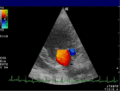

-

Anwendung des Doppler-Verfahrens bei einer Herzuntersuchung: Mitralklappeninsuffizienz -

Farb-Doppler und PW-Doppler. Innerhalb der Stenose ist wegen der hohen Flussgeschwindigkeit und des resultierenden Alias-Effekts die Geschwindigkeit in Blau kodiert. -